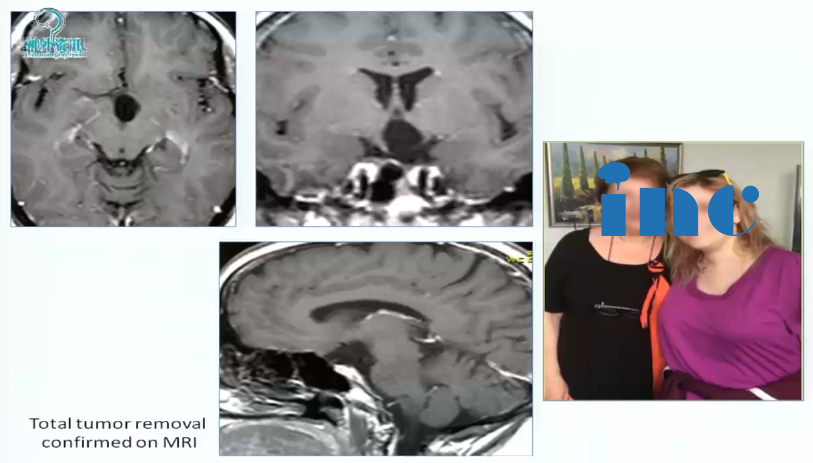

1、32岁女性,头疼、闭经、视野缺损,左侧视野象限盲,累及视路后部、下丘脑,脚前窝。病变完全位于中线,因此采用前纵裂入路。手术较终顺利全切。

图:术前MRI

术后情况:手术做的漂亮,解剖性全切,无神经损伤。